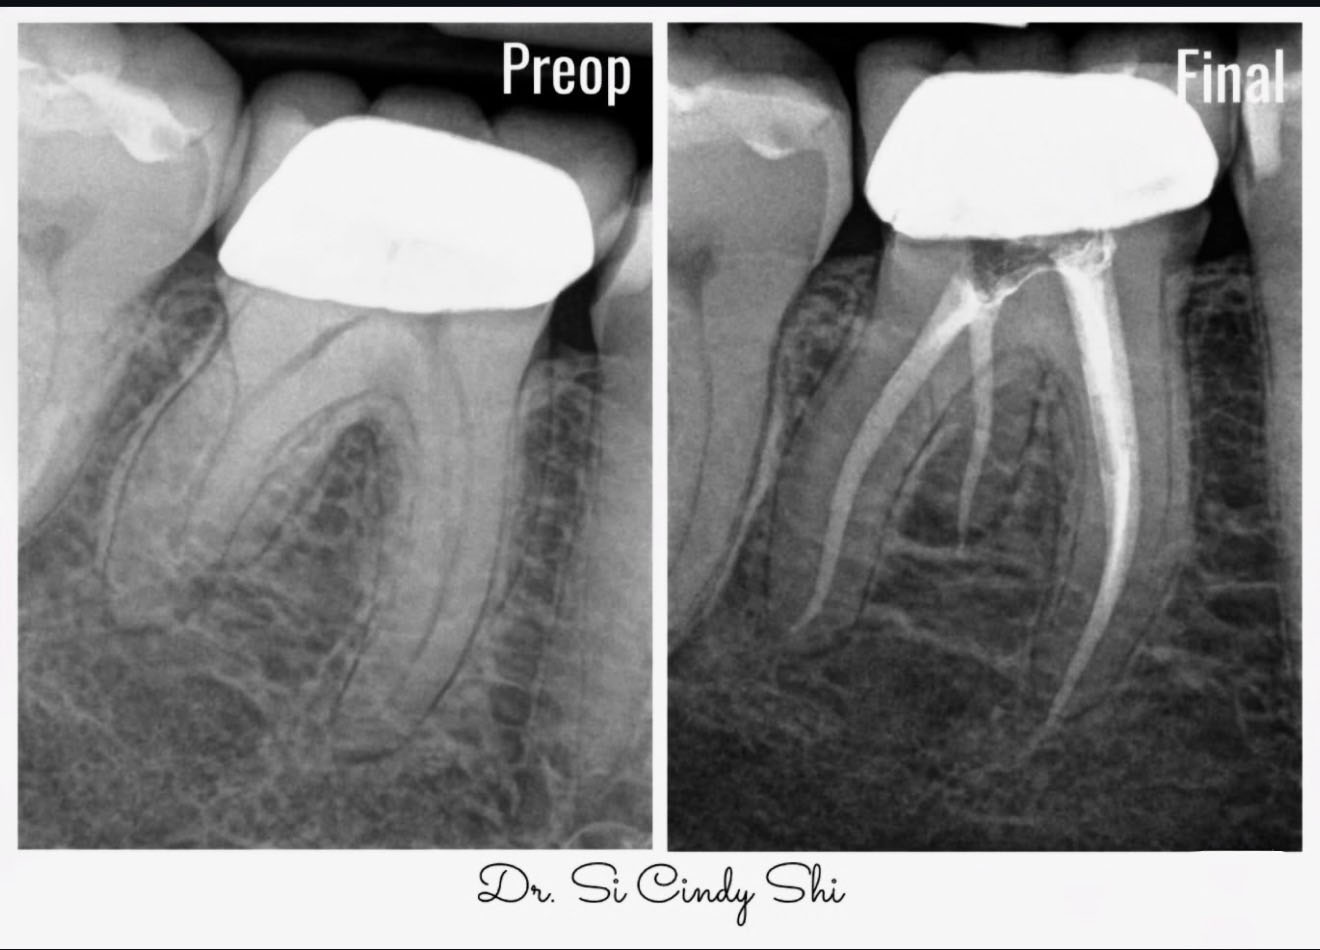

Root Canal Therapy

Relieve pain and save your natural tooth with precise, comfort-first treatment designed for calm, clear care.